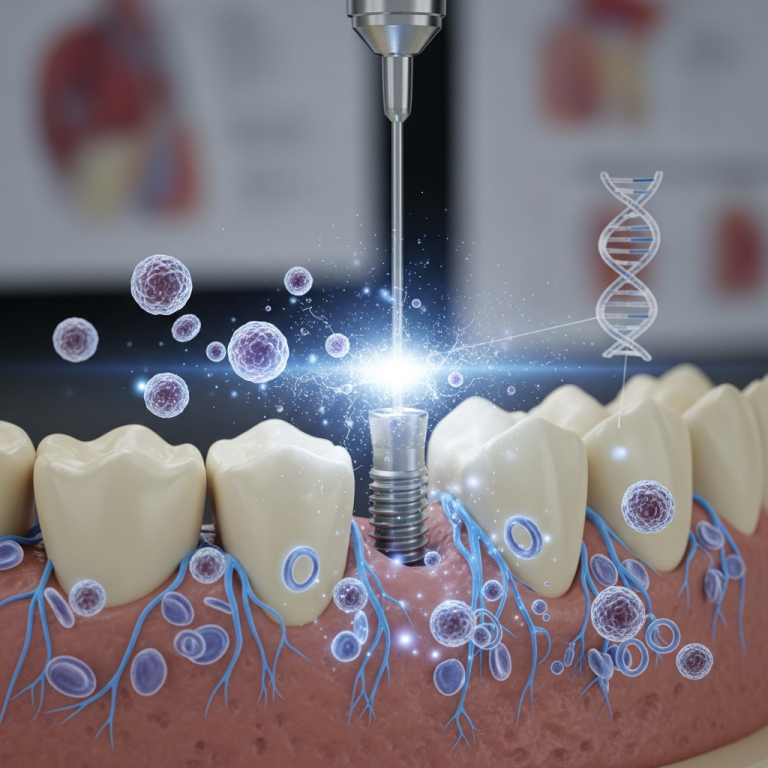

Implanturile dentare bicorticale sau bazale, o soluție pentru pacienții cu deficit osoos, implică o tehnică chirurgicală specifică, ceea ce se reflectă în structura costurilor.

- Tehnologia utilizată (planificare 3D, ghidaje chirurgicale).

Spre deosebire de implanturile tradiționale care necesită adesea adăugare de os, varianta bicorticală poate elimina acel cost suplimentar și perioada lungă de vindecare, justificând diferența de preț.

Este crucial să percepi acest cost ca o investiție în sănătatea orală pe termen lung. Studiile recente subliniază rata mare de succes și durabilitatea implanturilor bazale atunci când sunt aplicate corect.